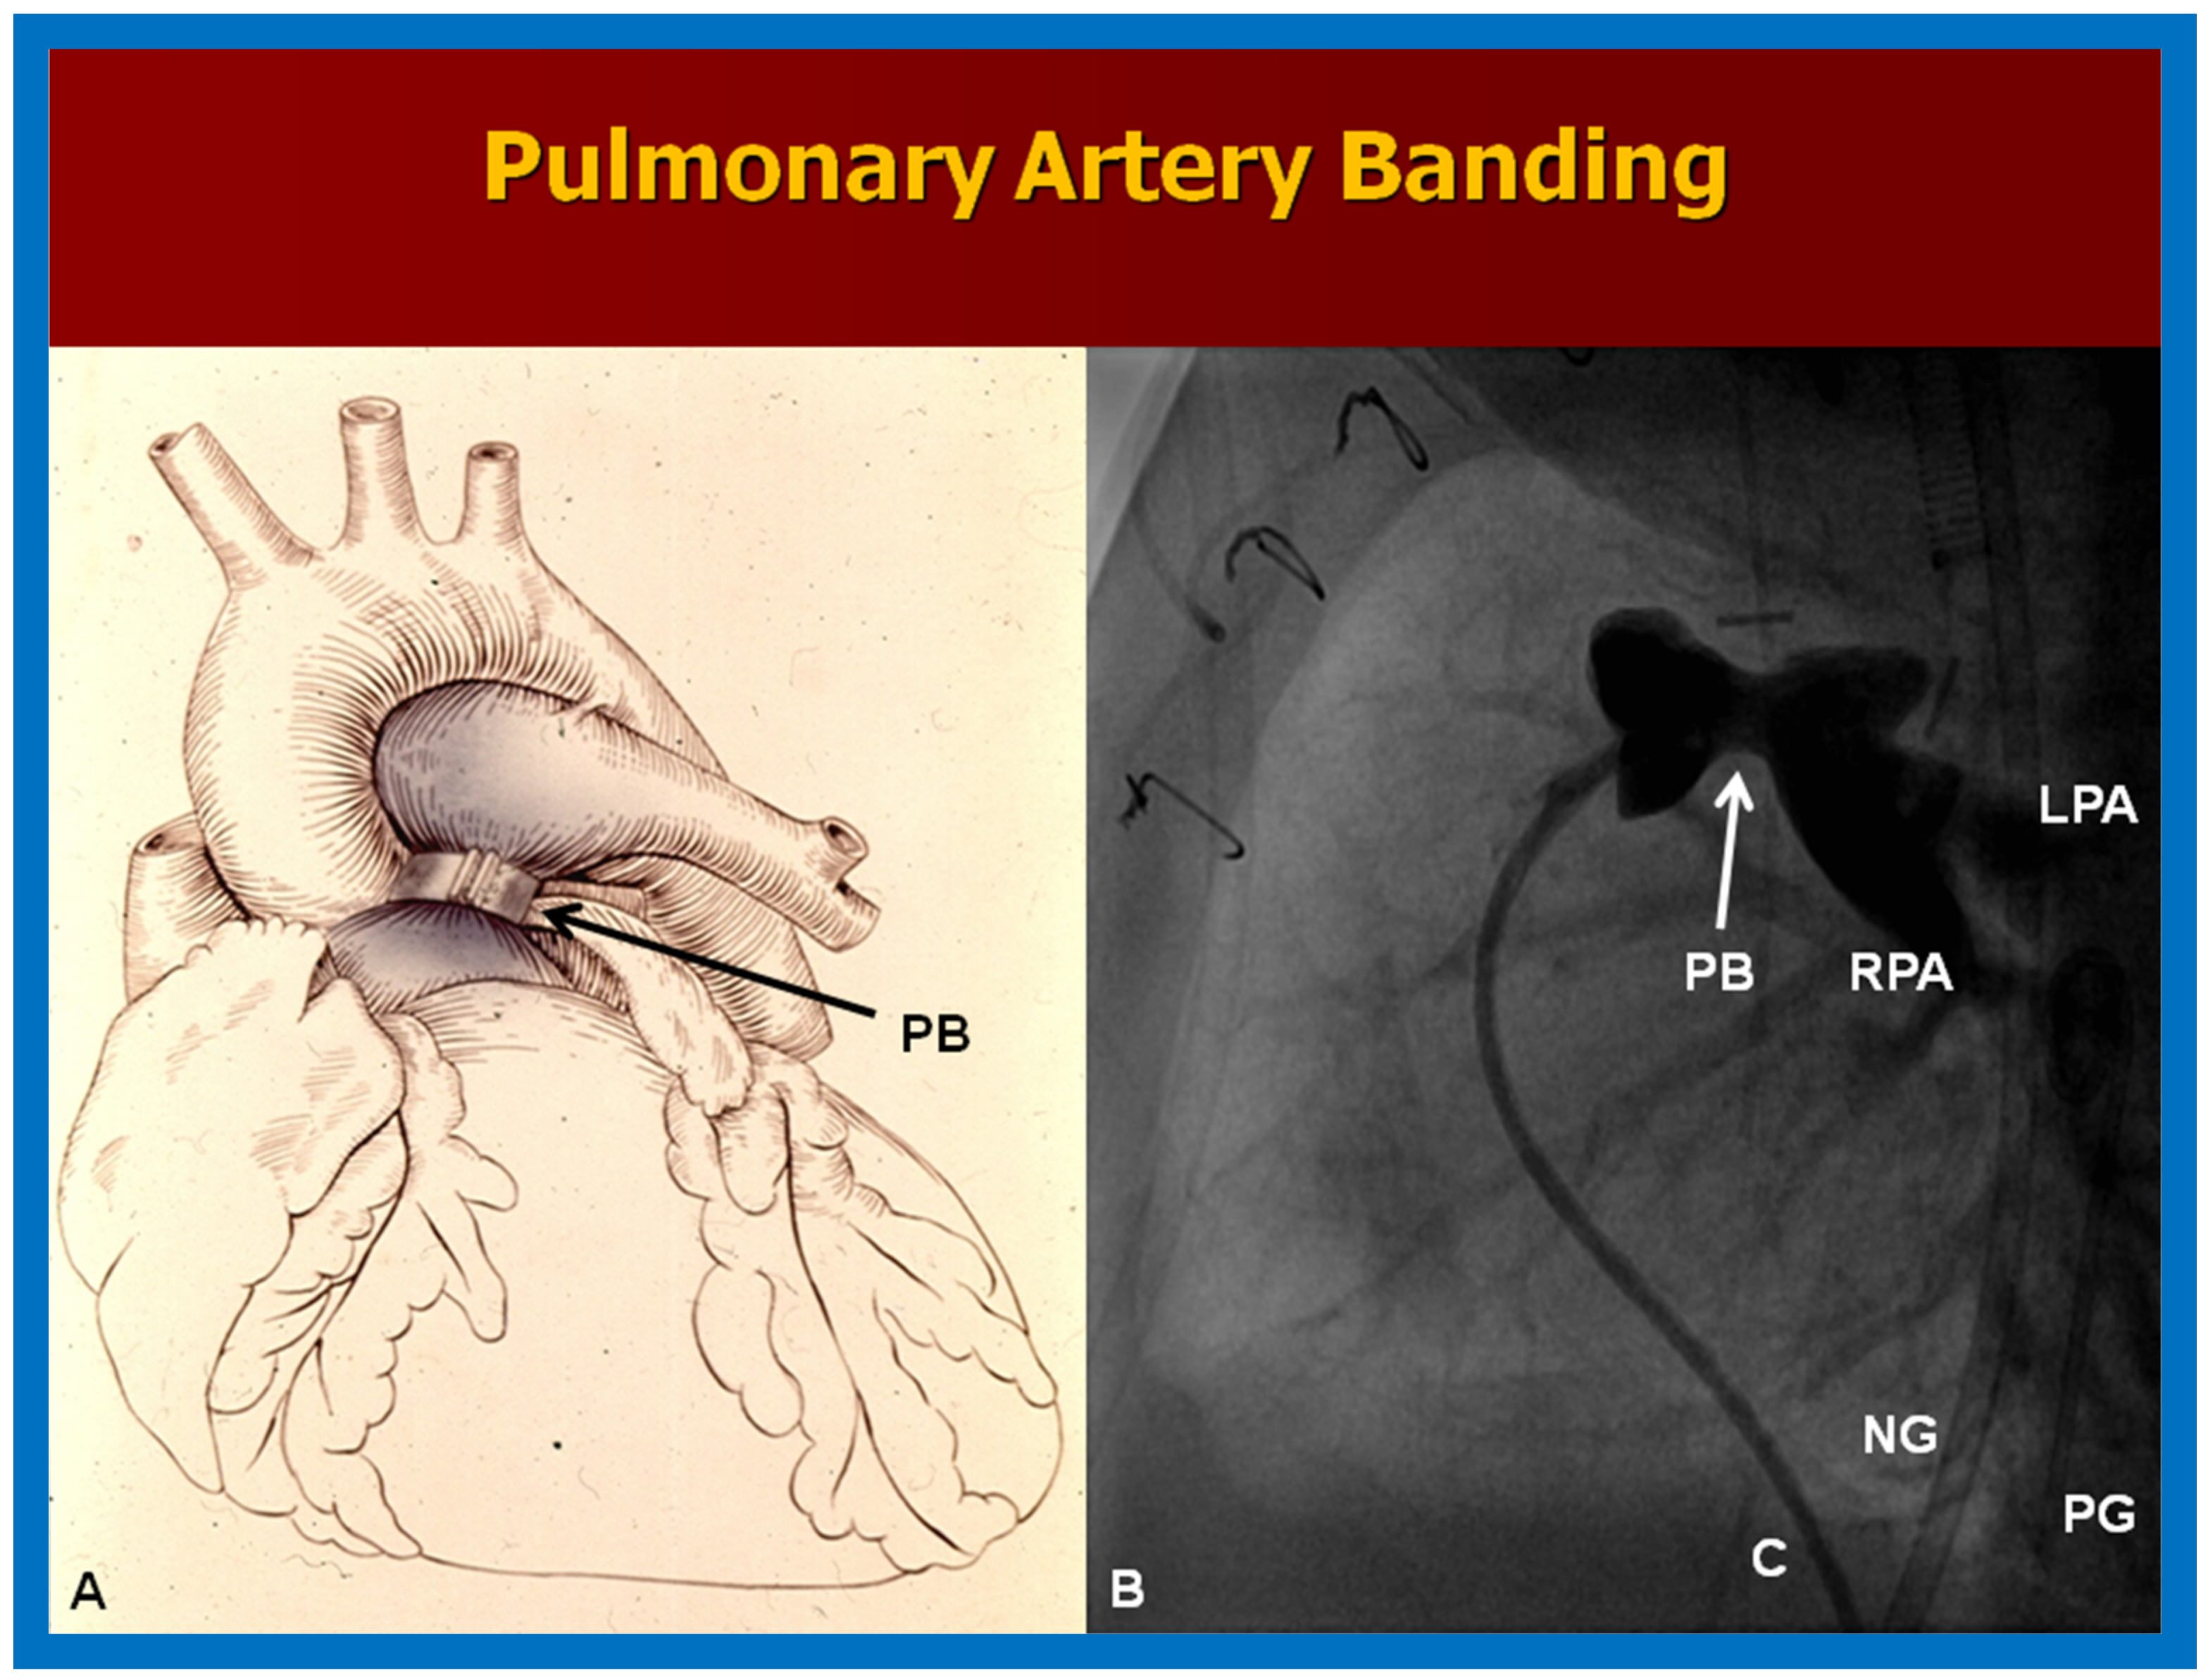

10.1.2. Elevated Pulmonary Blood Flow

10.1. Stage I